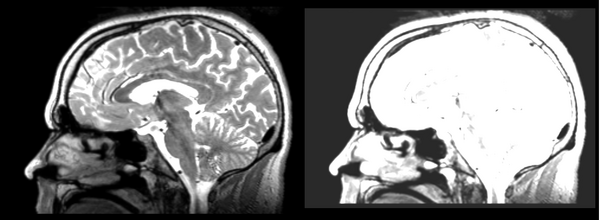

Affine

- 53-t2 -> 31-t1 = aff1

- aff1 -> 53-t2 = aff2

The image shows these side by side. The are nearly the same except for the loss of fine detail.

Linear

- 53-t2 -> 31-t1 = lin1

- lin1 -> 53-t2 = lin2

The image shows lin2 and 53-t2 side by side. The image shows there appears to be some change beyond loss of detail, possibly a L-R shift in the front.